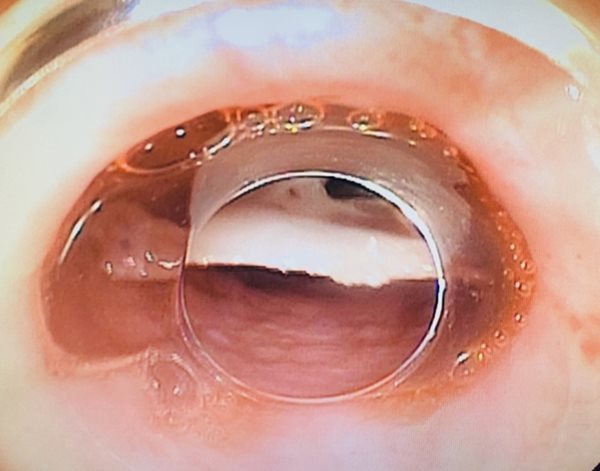

Hình ảnh nội soi cho thấy mảnh xương cắm vào thực quản bệnh nhân. Ảnh: Công an nhân dân |

Theo Công an nhân dân, chỉ mất 5 phút, các bác sĩ đã lấy được 1 xương cá "khủng" với kích thước 2,5x3cm có nhiều cạnh sắc trong thực quản của bệnh nhân. Đến sáng 25/6, bệnh nhân đã tỉnh, không sốt, giảm đau vùng cổ, nuốt được, uống sữa được, không nôn.